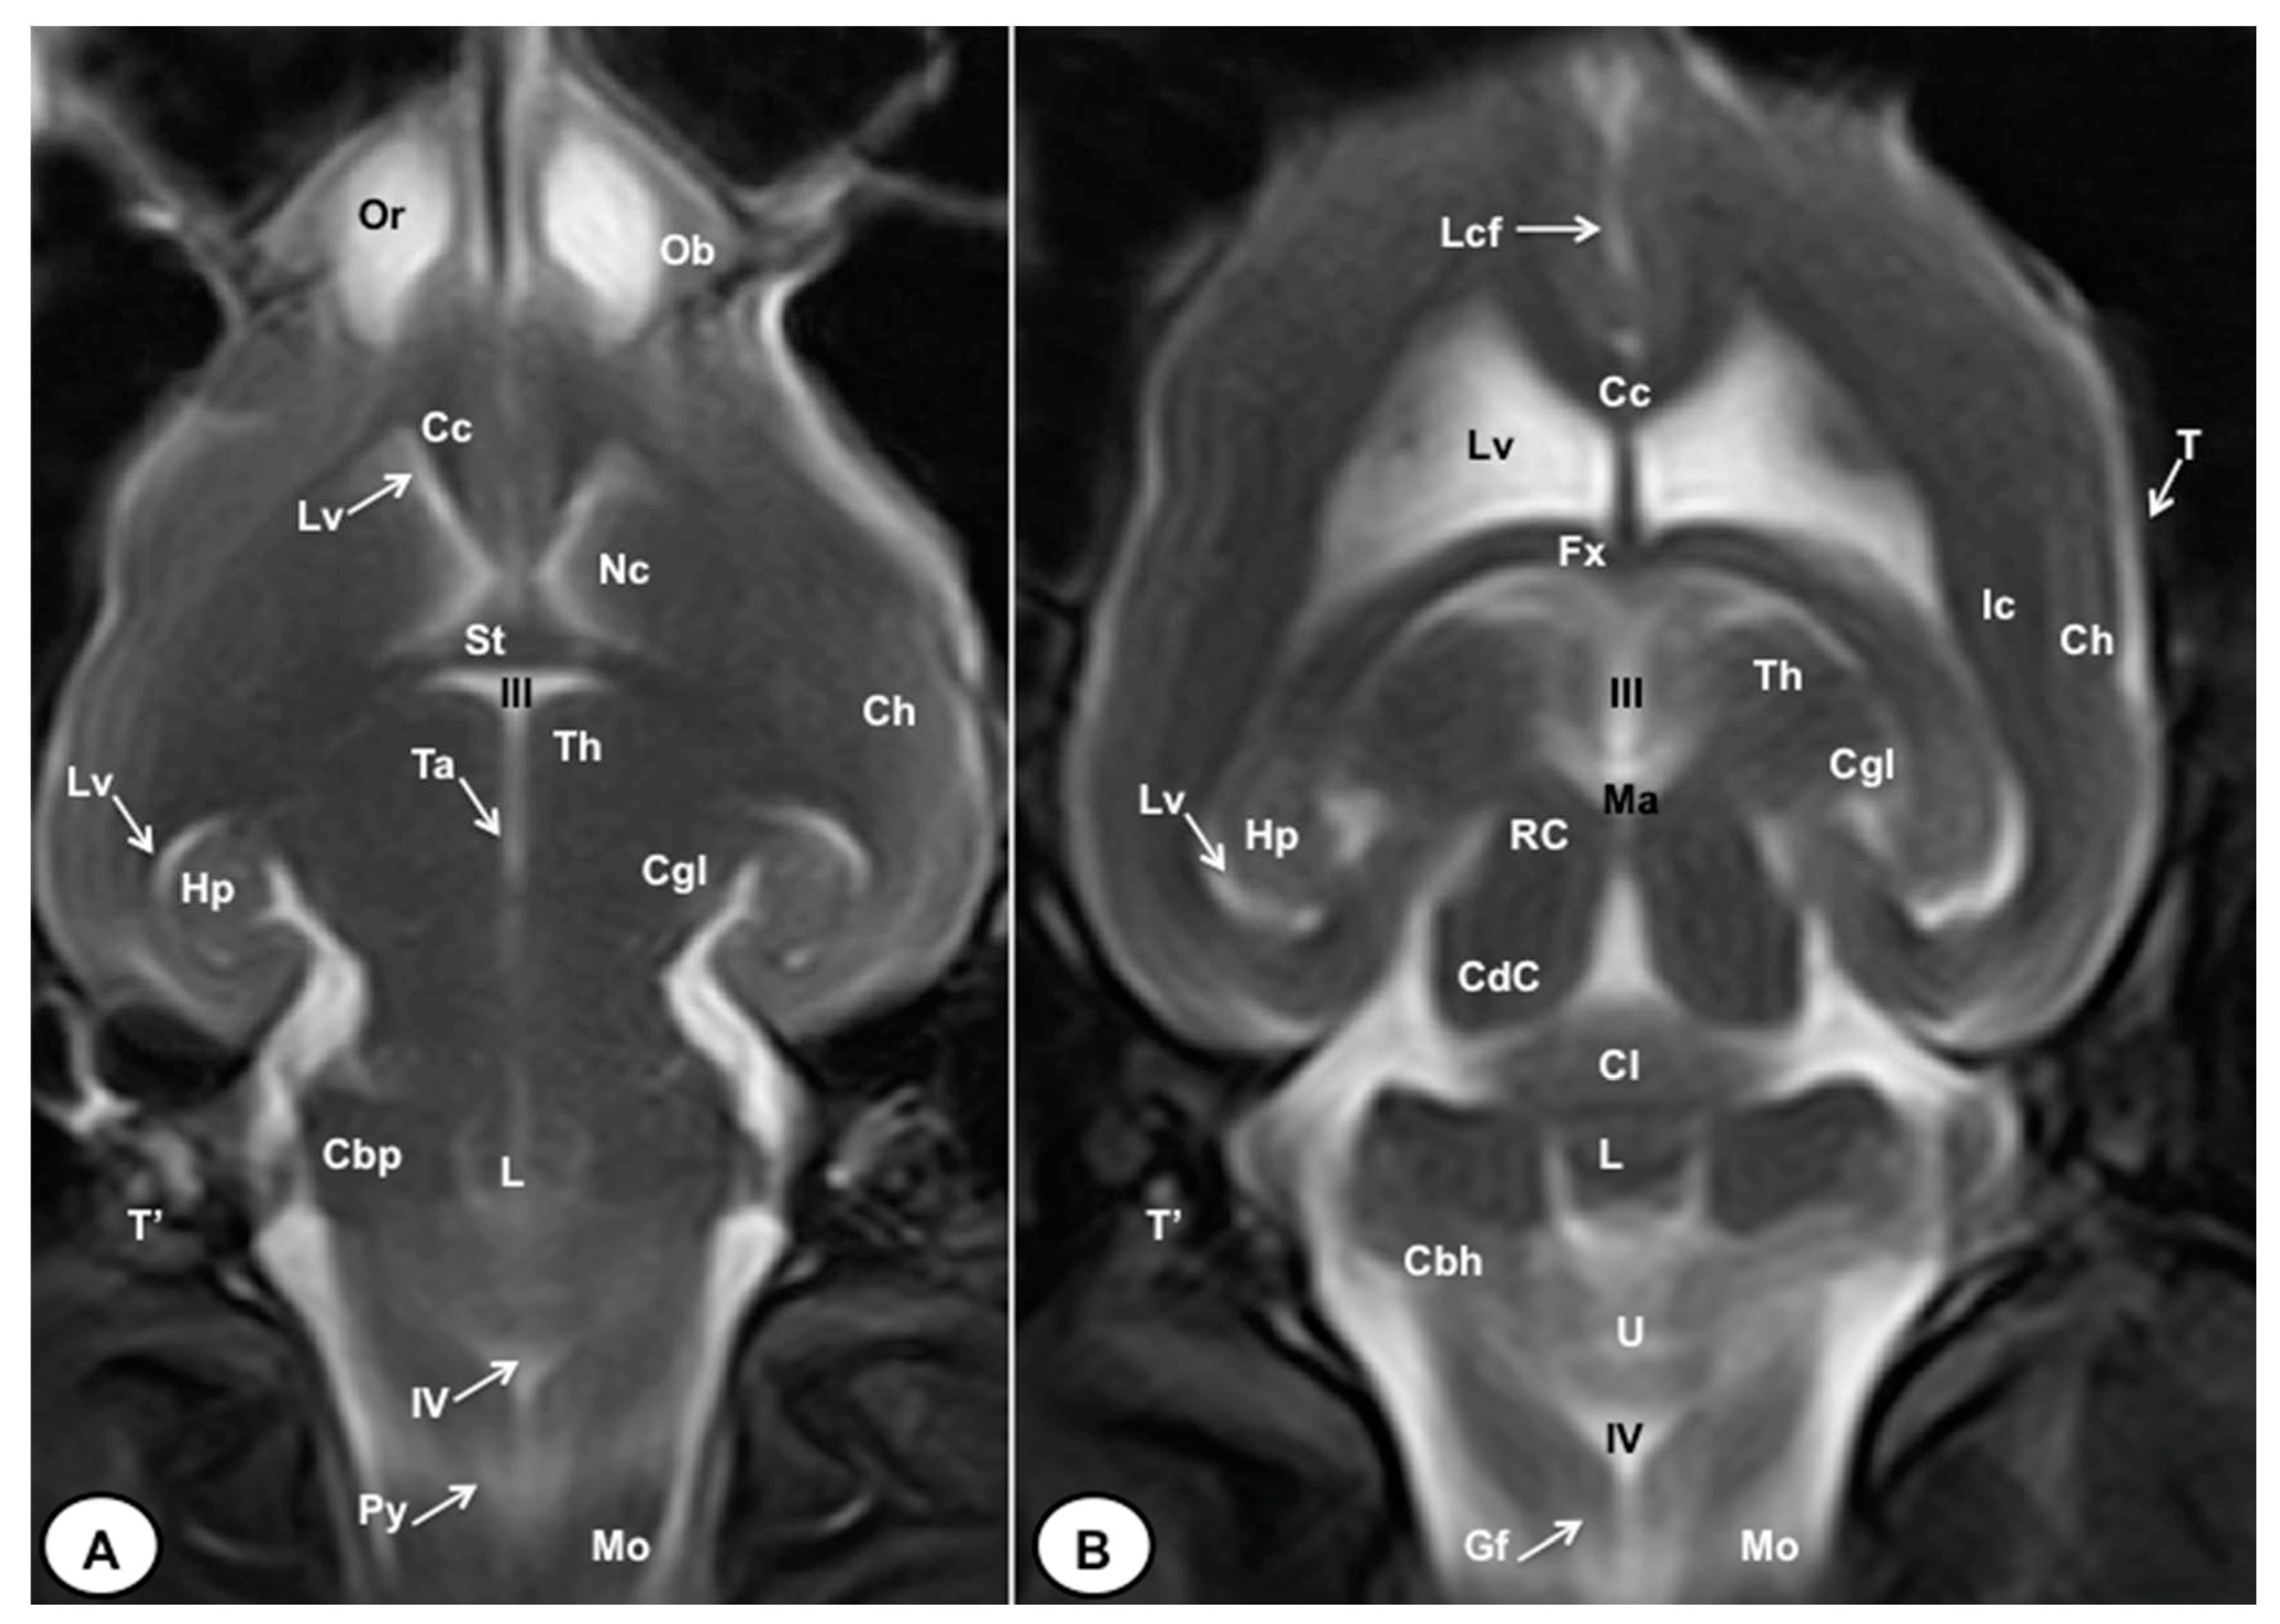

3.1. Anatomical gross-sections

3.2. Magnetic Resonance Imaging (MRI)